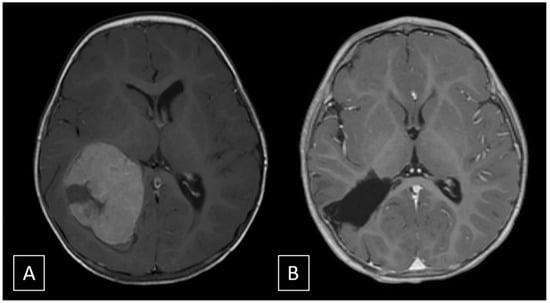

A 10-month-old female with regular neurological development and no previous medical history was admitted to our hospital for an acute onset of vomiting, followed by a progressive deterioration of her neurological status, requiring tracheal intubation. The computed tomography scan showed a large right intraventricular mass with recent bleeding associated with moderate midline shift. Magnetic resonance imaging (MRI) with contrast media and time-of-flight magnetic resonance angiography (ToF MRA) confirmed the presence of a large, hemorrhagic, intensely enhancing intraventricular mass, centered in the atrium of the right lateral ventricle, without invasion of the adjacent brain parenchyma, fed by a moderately enlarged anterior choroidal artery (Figure 1). Whole spine MRI excluded signs of cerebrospinal fluid seeding. The patient was scheduled for the following day to perform endovascular embolization and surgical excision.

Figure 1. (A) Gradient-echo image shows intralesional, perilesional and intraventricular hemorrhagic components. (B,C) T2 axial (B) and Volume Rendering of ToF MRA (C) show the course of the anterior choroidal artery. The shifted white line represents, schematically, the course of the artery; dashed arrows indicate the exact location of the highlighted vessel. Segment 1 is the cisternal portion of the artery which courses across the carotid, crural and ambient cysterns, up to the choroidal fissure, where it enters the ventricle; the asterisk * corresponds to the plexal point that marks the entrance in the ventricle, and segment 2 is the intraventricular segment. Segment 3 is the tumoral segment of the artery running along the surface of the tumor (see Figure 4 for the complete anatomical description).